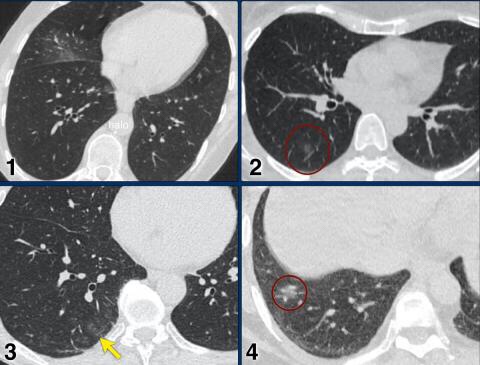

Examples of CO-RADS 3. Click to enlarge.

Case 5

7 day of complaints.

CT: multifocal consolidations with surrounding GGO.

PCR negative.

Case 6

Recent Influenza A . History of pulmonary hypertension.

Started coughing again.

CT: bilateral central consolidations with diffuse GGO.

Re-test: COVID-19 PCR: negative and Influenza A: positive.